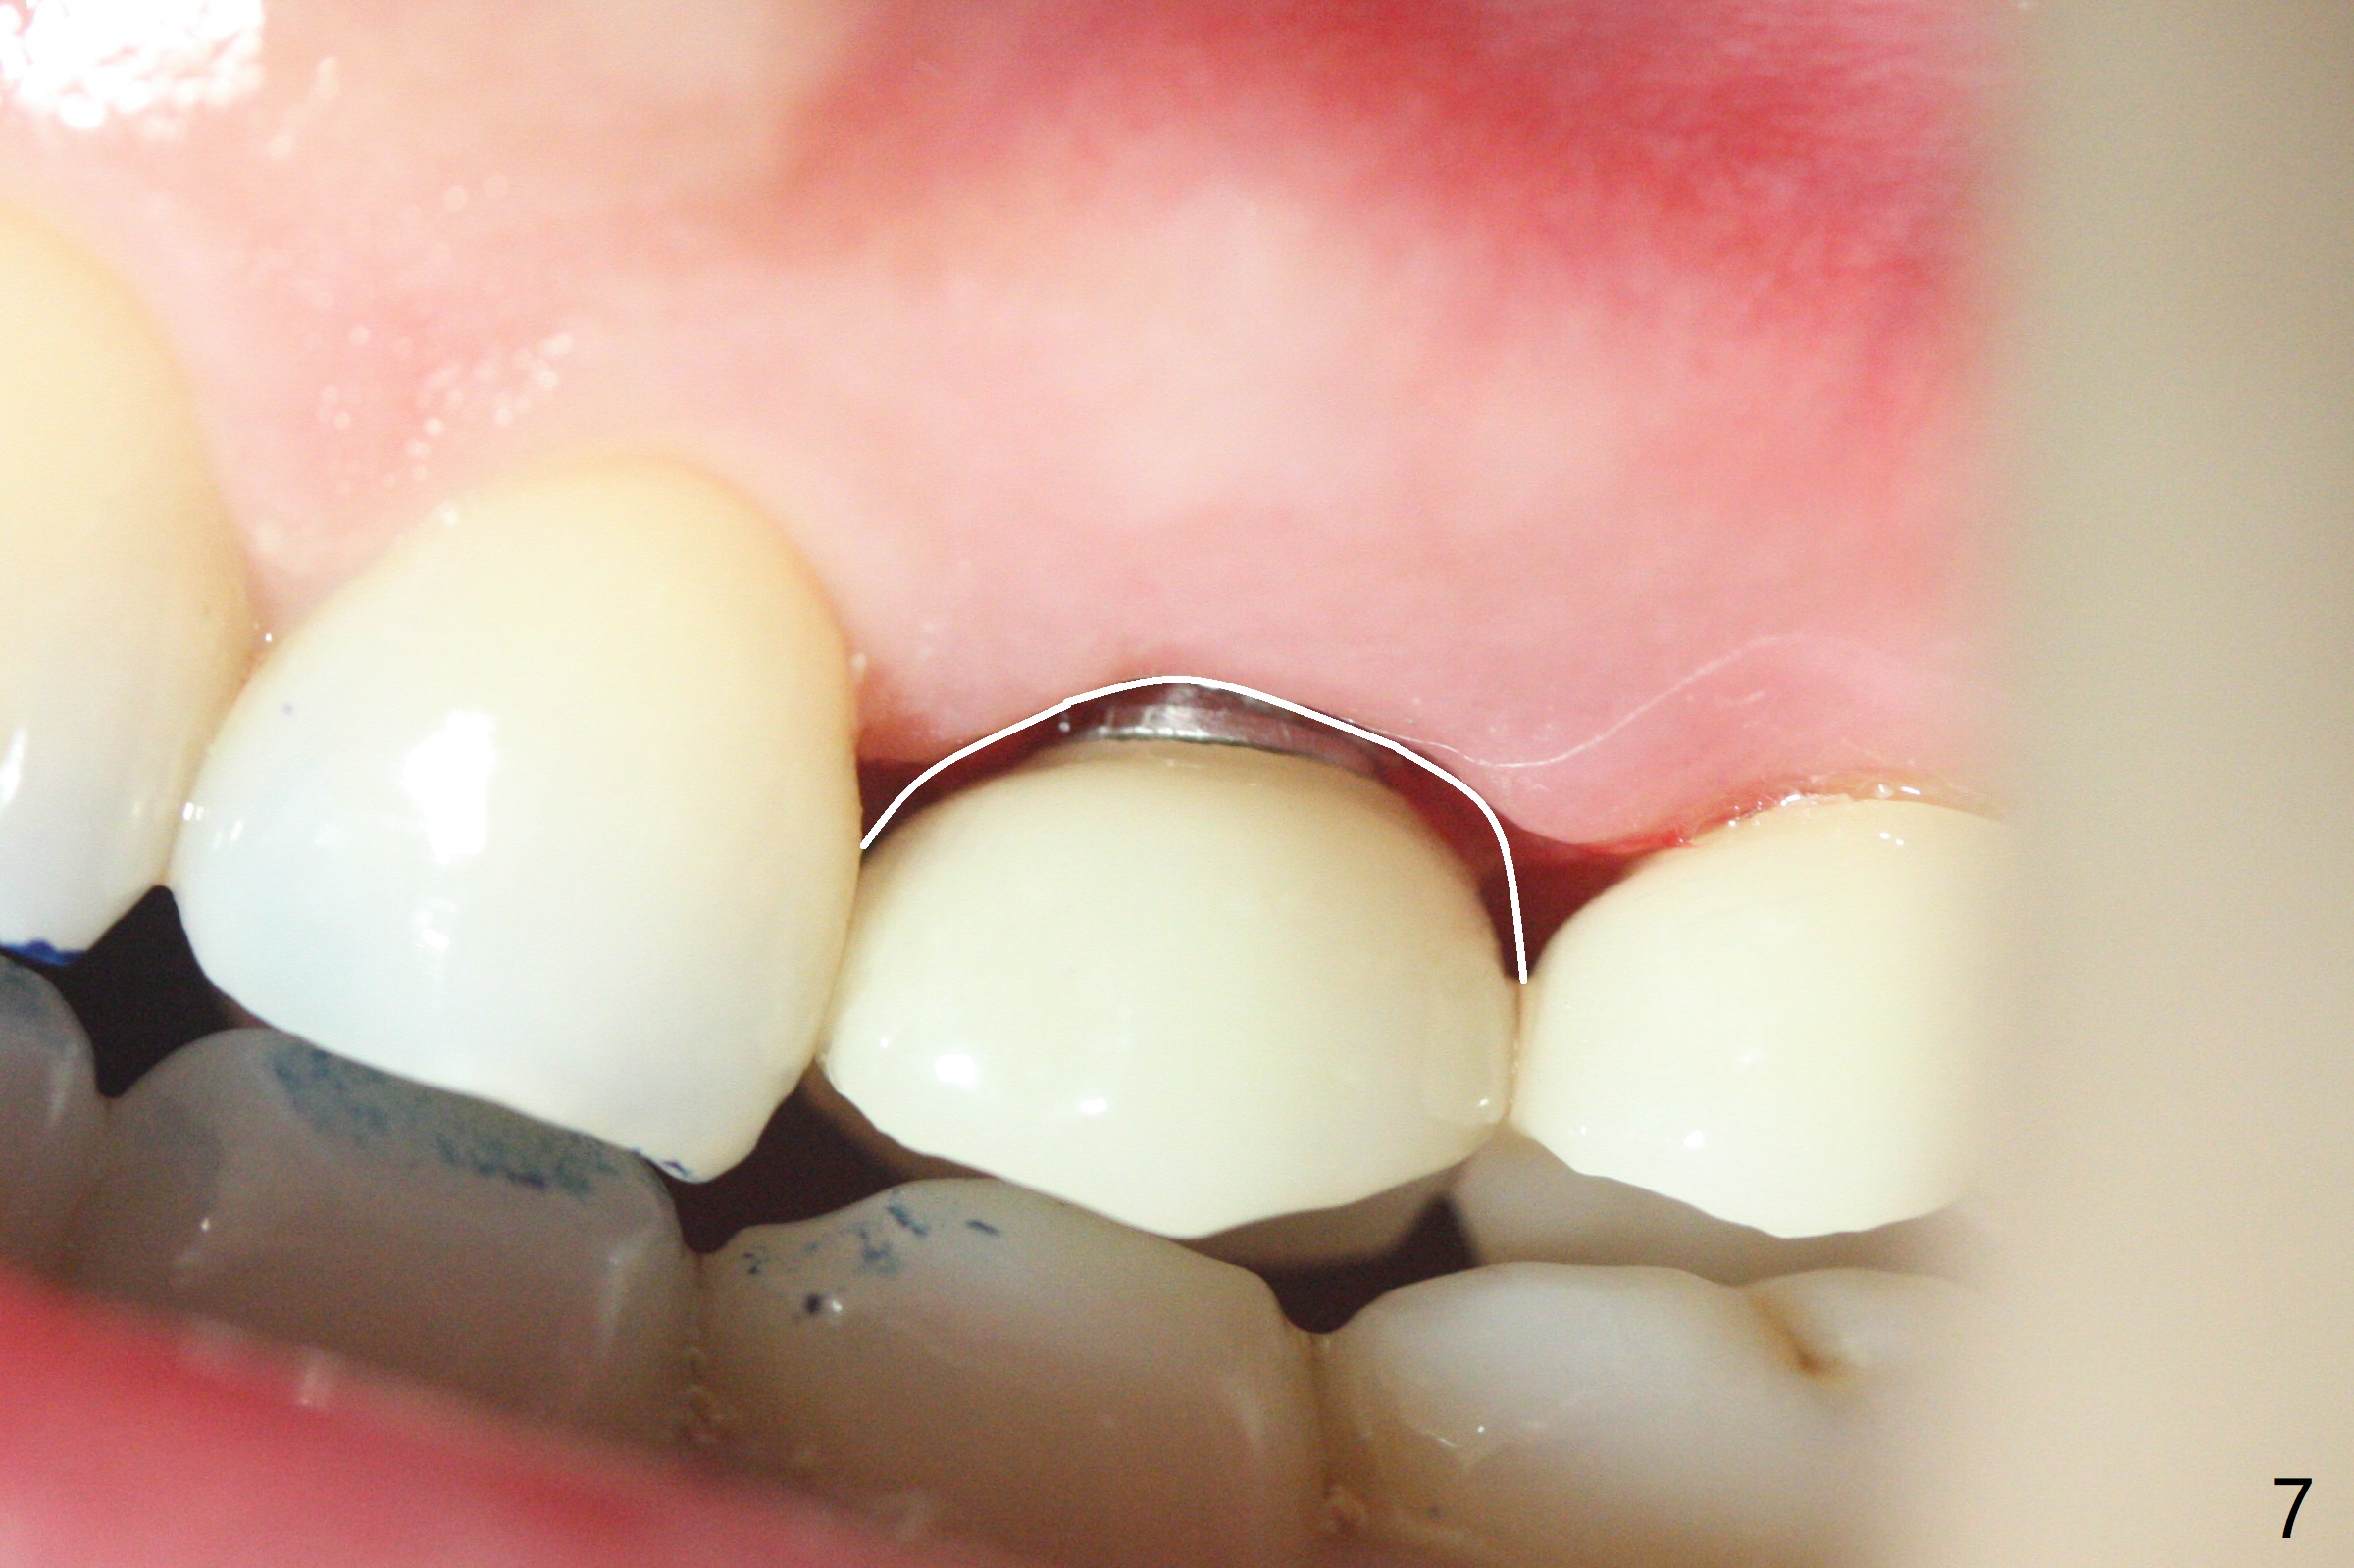

Due to misinterpretation of drill sequence, osteotomy is overprepared in depth (1.5 to 3 mm). When a 4x11 mm dummy implant is placed with > 50 Ncm (Fig.1,2), over placement is ignored. A 4x13 mm final implant is placed with fairly good torque, but it is deeper than expected. When it is backed up, primary stability is lost, in spite of placement of allograft in the osteotomy. Final torque is 15 Ncm. When a 4.5x4(2) mm abutment is placed, the underlying implant turns (Fig.3). A splinted provisional is fabricated at #13 and 14. RCT is retreated 5 months postop (Fig.4 *). An abutment with longer cuff is placed before impression (8.5 months postop, Fig.5). When the crowns of #13 and 14 are delivered, the former looks short and noncosmetic, although the gingiva will grow downward to close the gap (Fig.6). Ideally the gap should be closed with porcelain with overhang (Fig.7).